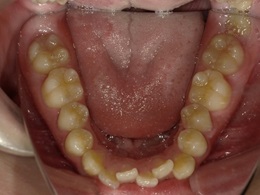

治療前下顎

治療中下顎

治療後下顎